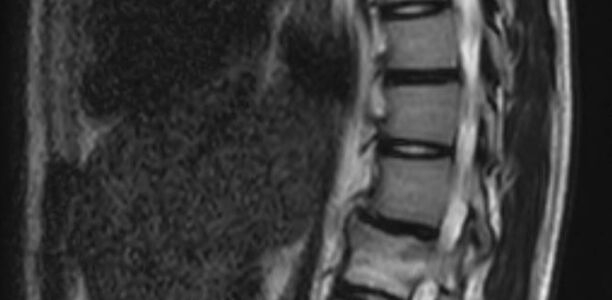

Anfänglich starke Rückenschmerzen, obwohl kein Trauma vorangegangen war, und 9 Monate später eine neu aufgetretene Hyperkyphose der Brustwirbelsäule mit zunehmenden Schmerzen. Wie lautet Ihre Diagnose?

Ein 16-jähriges Mädchen mit Rückenschmerzen und Kyphose